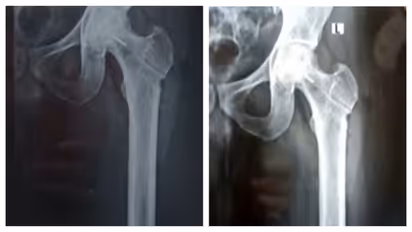

തിരുവനന്തപുരം ജൂബിലി മെമ്മോറിയൽ ആശുപത്രിക്കെതിരെ ഗുരുതര ചികിത്സാപിഴവ് പരാതി. ഇടുപ്പ് എല്ലിൽ ശസ്ത്രക്രിയ ചെയ്യുന്നതിനിടെയാണ് ചികിത്സ പിഴവുണ്ടായിരിക്കുന്നത്. രക്തയോട്ടം കൂട്ടാനുള്ള ശസ്ത്രക്രിയക്കിടെ ഡ്രിൽ ബിറ്റ് ഒടിഞ്ഞു കയറുകയായിരുന്നു. മലയിൻകീഴ് സ്വദേശി ജിജിൻ ജോസിൻെറ ഇടത് ഇടുപ്പ് എല്ലിലാണ് ഡ്രിൽ ബിറ്റ് ഒടിഞ്ഞു കയറിയത്. ജിജിൻെറ പരാതിയിൽ കൻോൺമെന്റ് പൊലീസ് കേസെടുത്തിട്ടുണ്ട്. ലോഹ കഷണം നീക്കം ചെയ്യാനാകില്ലെന്നും ലോഹ കഷണം ഇരിക്കുന്നതിനാൽ പ്രശ്നങ്ങളുണ്ടാകില്ലെന്നും രോഗിയെ അറിയിച്ചതാണെന്ന് ആശുപത്രി അധികൃതർ വ്യക്തമാക്കുന്നു.